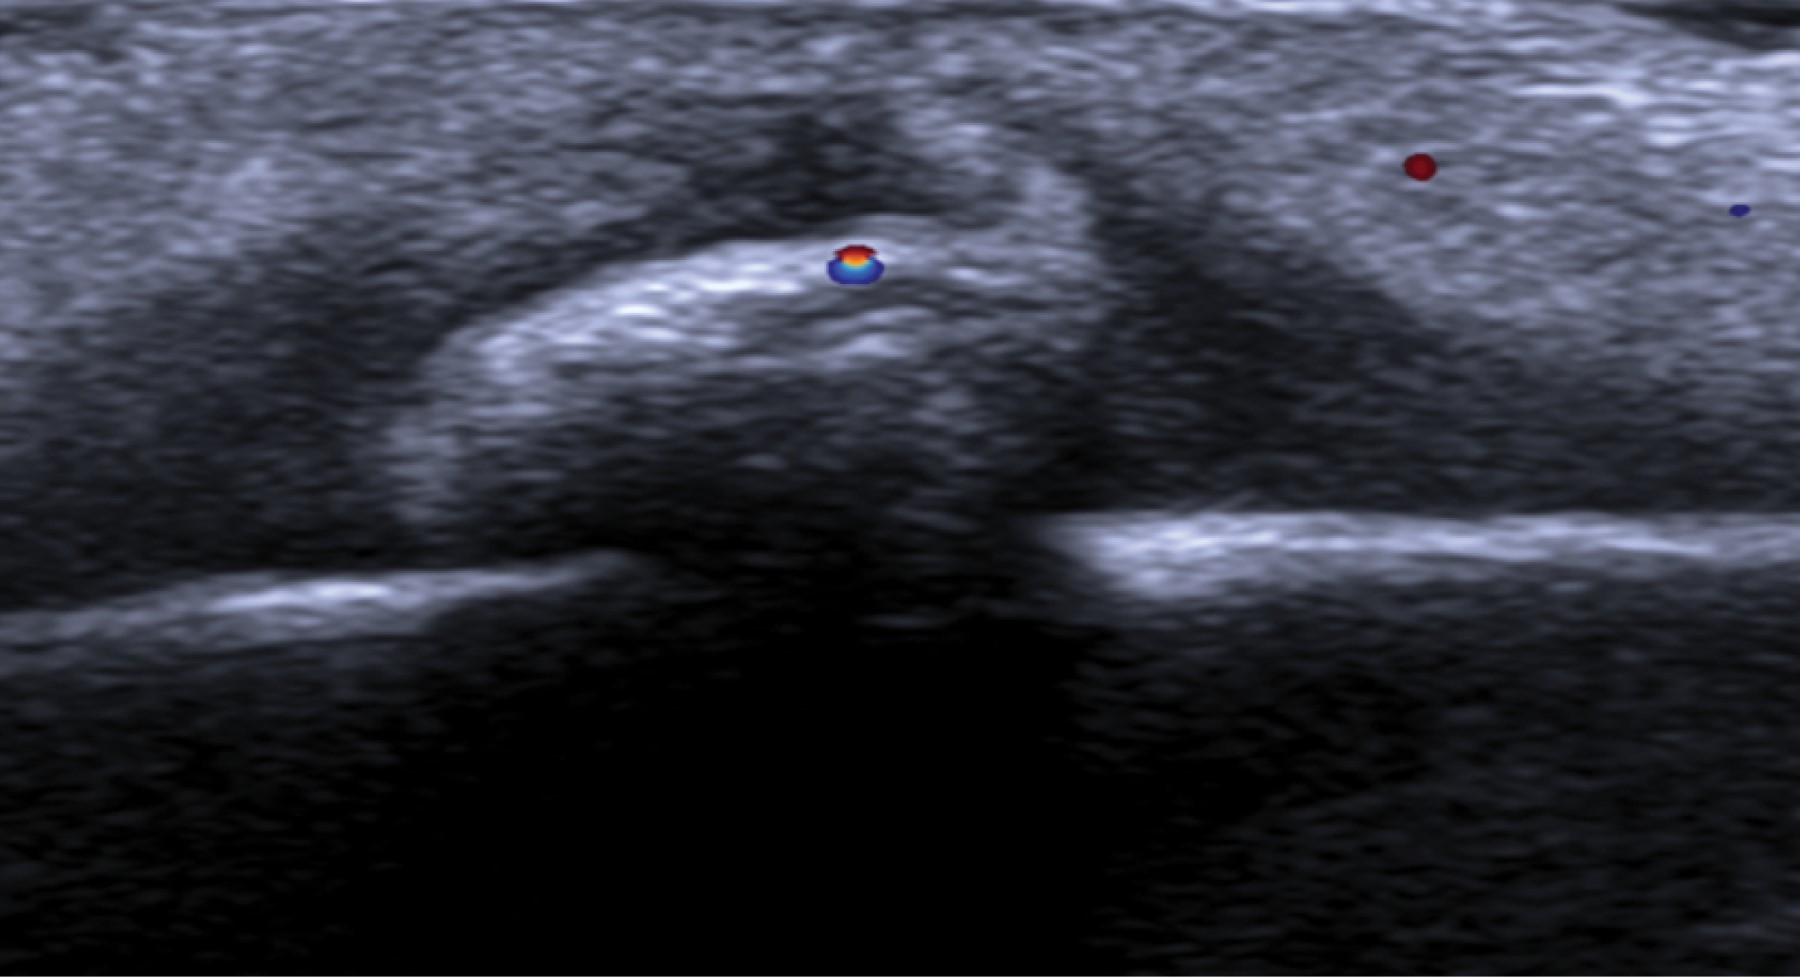

Paciente femenino de dos años que acude con médico pediatra por presentar pápula subcutánea en la región frontal, localizada en la piel cabelluda con aumento de volumen y eritema sin dolor a la palpación. Después de la revisión clínica la paciente fue enviada para la realización de ultrasonido (Figura 1), con sospecha de cuerpo extraño versus hematoma. Por último, es explorada quirúrgicamente obteniendo con claridad la larva de la mosca (Figura 2). La paciente tuvo una evolución favorable y fue dada de alta definitiva a las 72 horas.

El diagnóstico de lesiones subcutáneas incluye al ultrasonido como primera opción. Permite una valoración rápida, inocua y saber si la lesión es sólida o quística, su localización y eventual penetración a planos más profundos y su vascularidad.

En este caso la primera opción diagnóstica fue un cuerpo extraño, resultando una inusual forma de parasitosis cutánea en población no susceptible secundaria a larvas de mosca de la especie Dermatobia hominis.

Figura 1